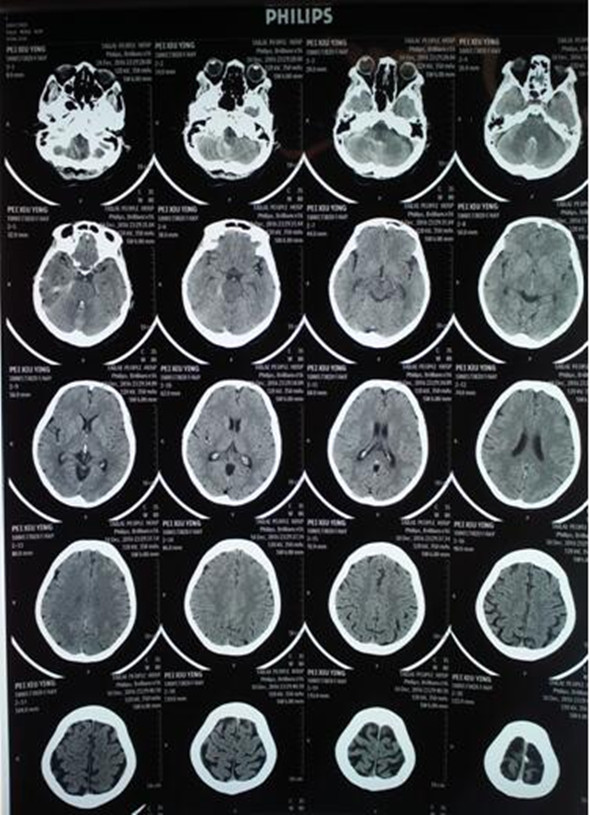

12月11日,对于裴女士及家人来说是不幸的。裴女士在入院前一天,无明显诱因突发出现头痛、头晕,伴恶心且呕吐数次(呕吐物为胃内容物),有二便失禁、意识不清、问话不答的症状。家人紧急将裴女士送入我院,行头部CT检查诊断为:蛛网膜下腔出血/动脉瘤破裂。

术前头部CT